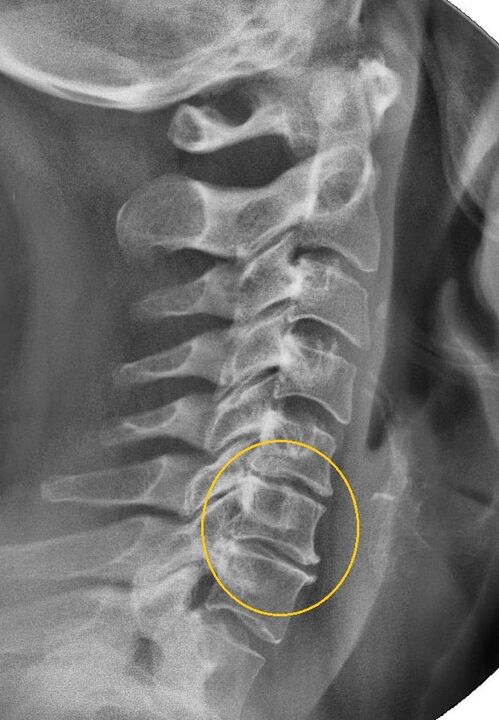

The most informative diagnostic procedure is radiography.Pathologies of the 1st degree correspond to the 1st or 2nd radiological stage.The resulting images visualize typical signs of illness.

| X-ray stages of cervical osteochondrosis of the 1st degree | Characteristic signs |

|---|---|

| Stage 1 | Minor changes in the curvature of the spine in the neck area, affecting one or more segments |

| Stage 2 | Slight thickening of the intervertebral discs, deformation of the uncinate processes, straightening of the lordosis, minor growths of the bone structures |